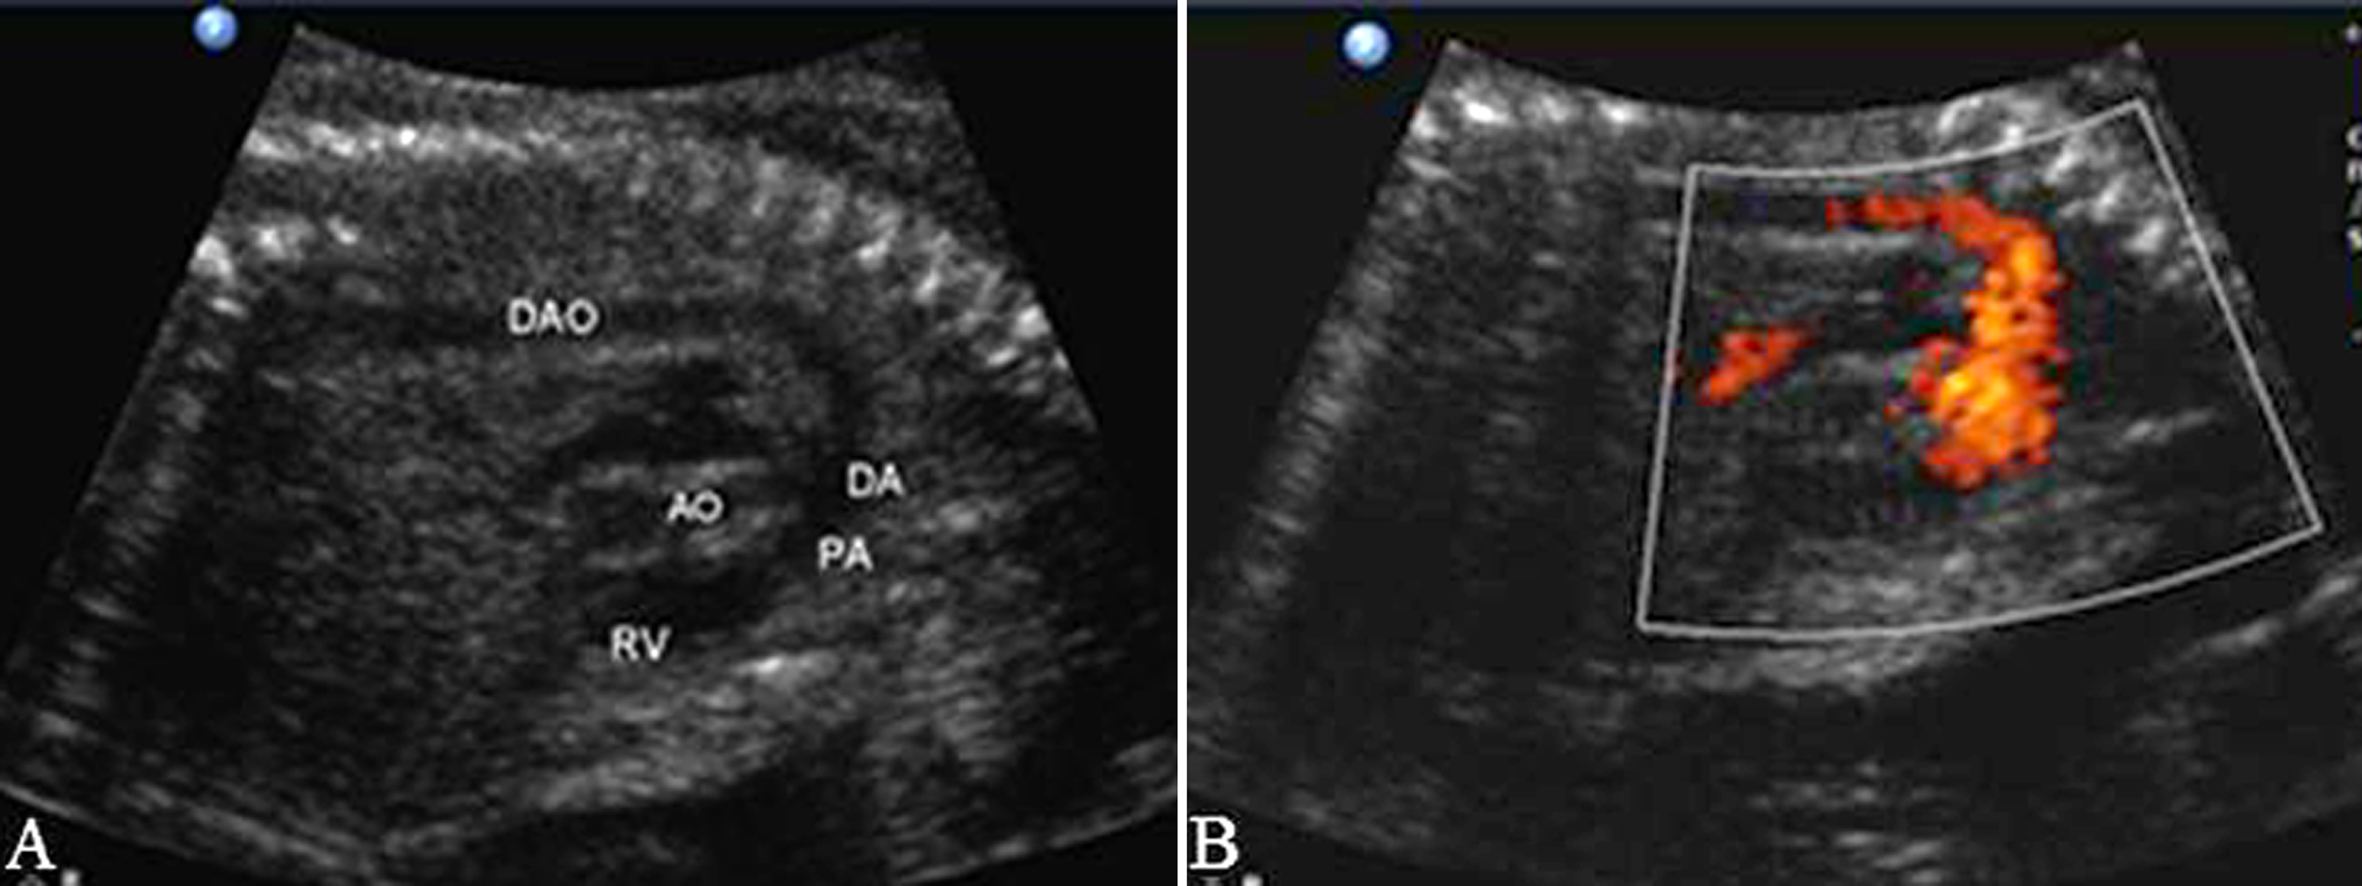

1.主动脉(AO)瓣及AO根部 多个切面都可显示AO根部和LV相连的情况,血流显示清楚。在色彩上,AO要比肺动脉(PA)鲜艳,血流速度比PA内的血流速度快,其原因可能与AO内径较细、远端血流阻力较PA的阻力小有关(图2、图3)。

图2 左室流出道切面观(A)及血流(B)

AO的血流频谱为窄带单峰,上升支较下降支快。由于升主动脉和主动脉弓的血液主要来自胎儿的LV,在心室的舒张期可以发现血流中断,形成有空窗的基线。